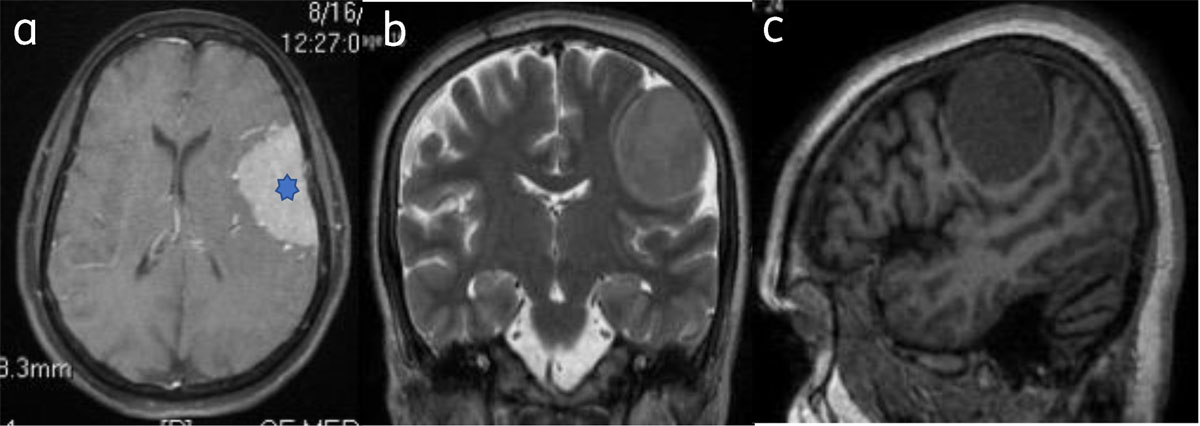

Figure 1

Classical meningioma: – (a) Axial post contrast image show enhancing broad based extra-axial lesion (star). Lesion is isointense on T2W (b) and T1W (c) to the gray matter.